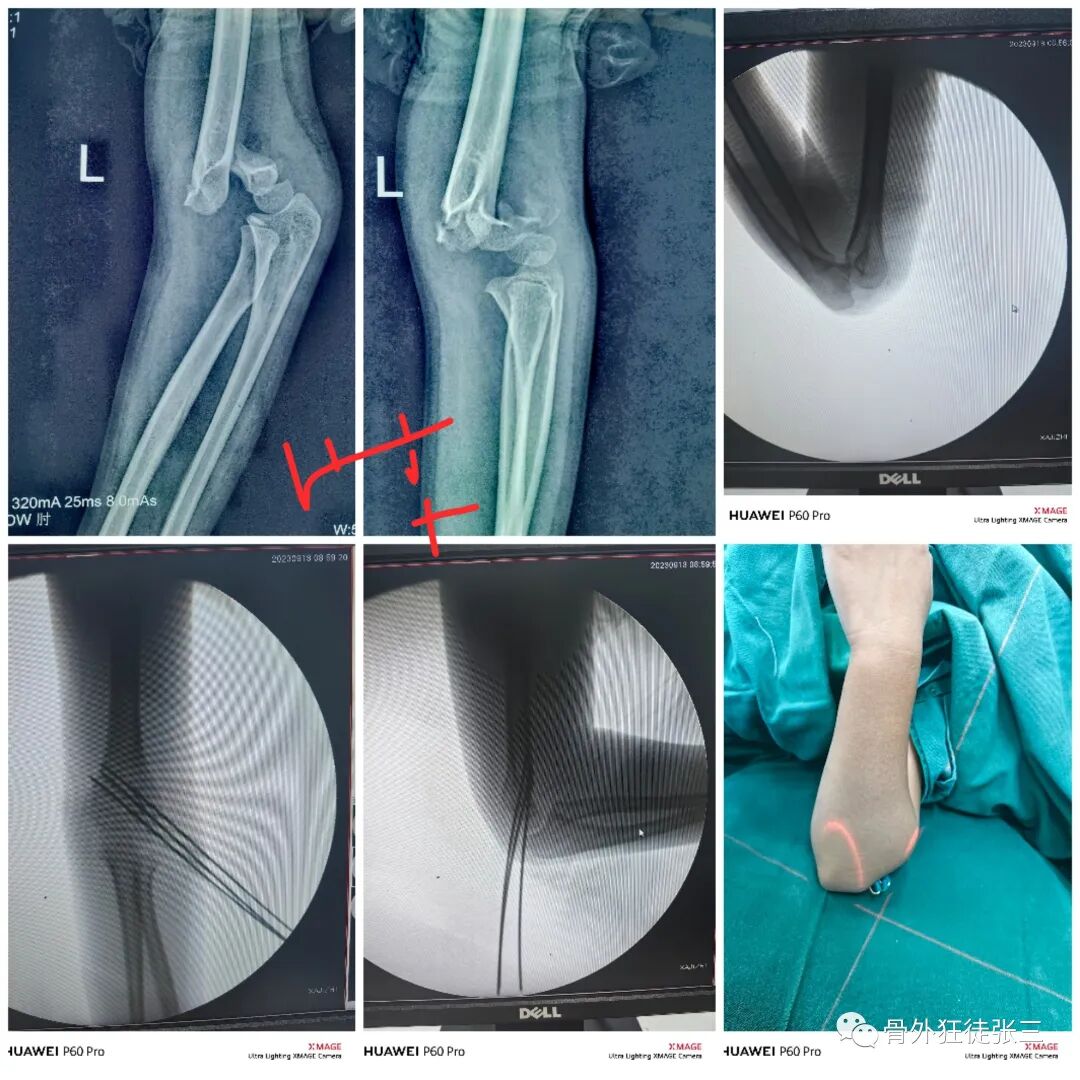

病例14,儿童髁上骨折零切开,桡侧三枚针发散固定

病例15,儿童髁上骨折零切开,

病例16,儿童髁上骨折零切开

病例17,低位髁上骨折零切开

病例18,第一掌骨基底部骨折,闭合复位,克氏针支架